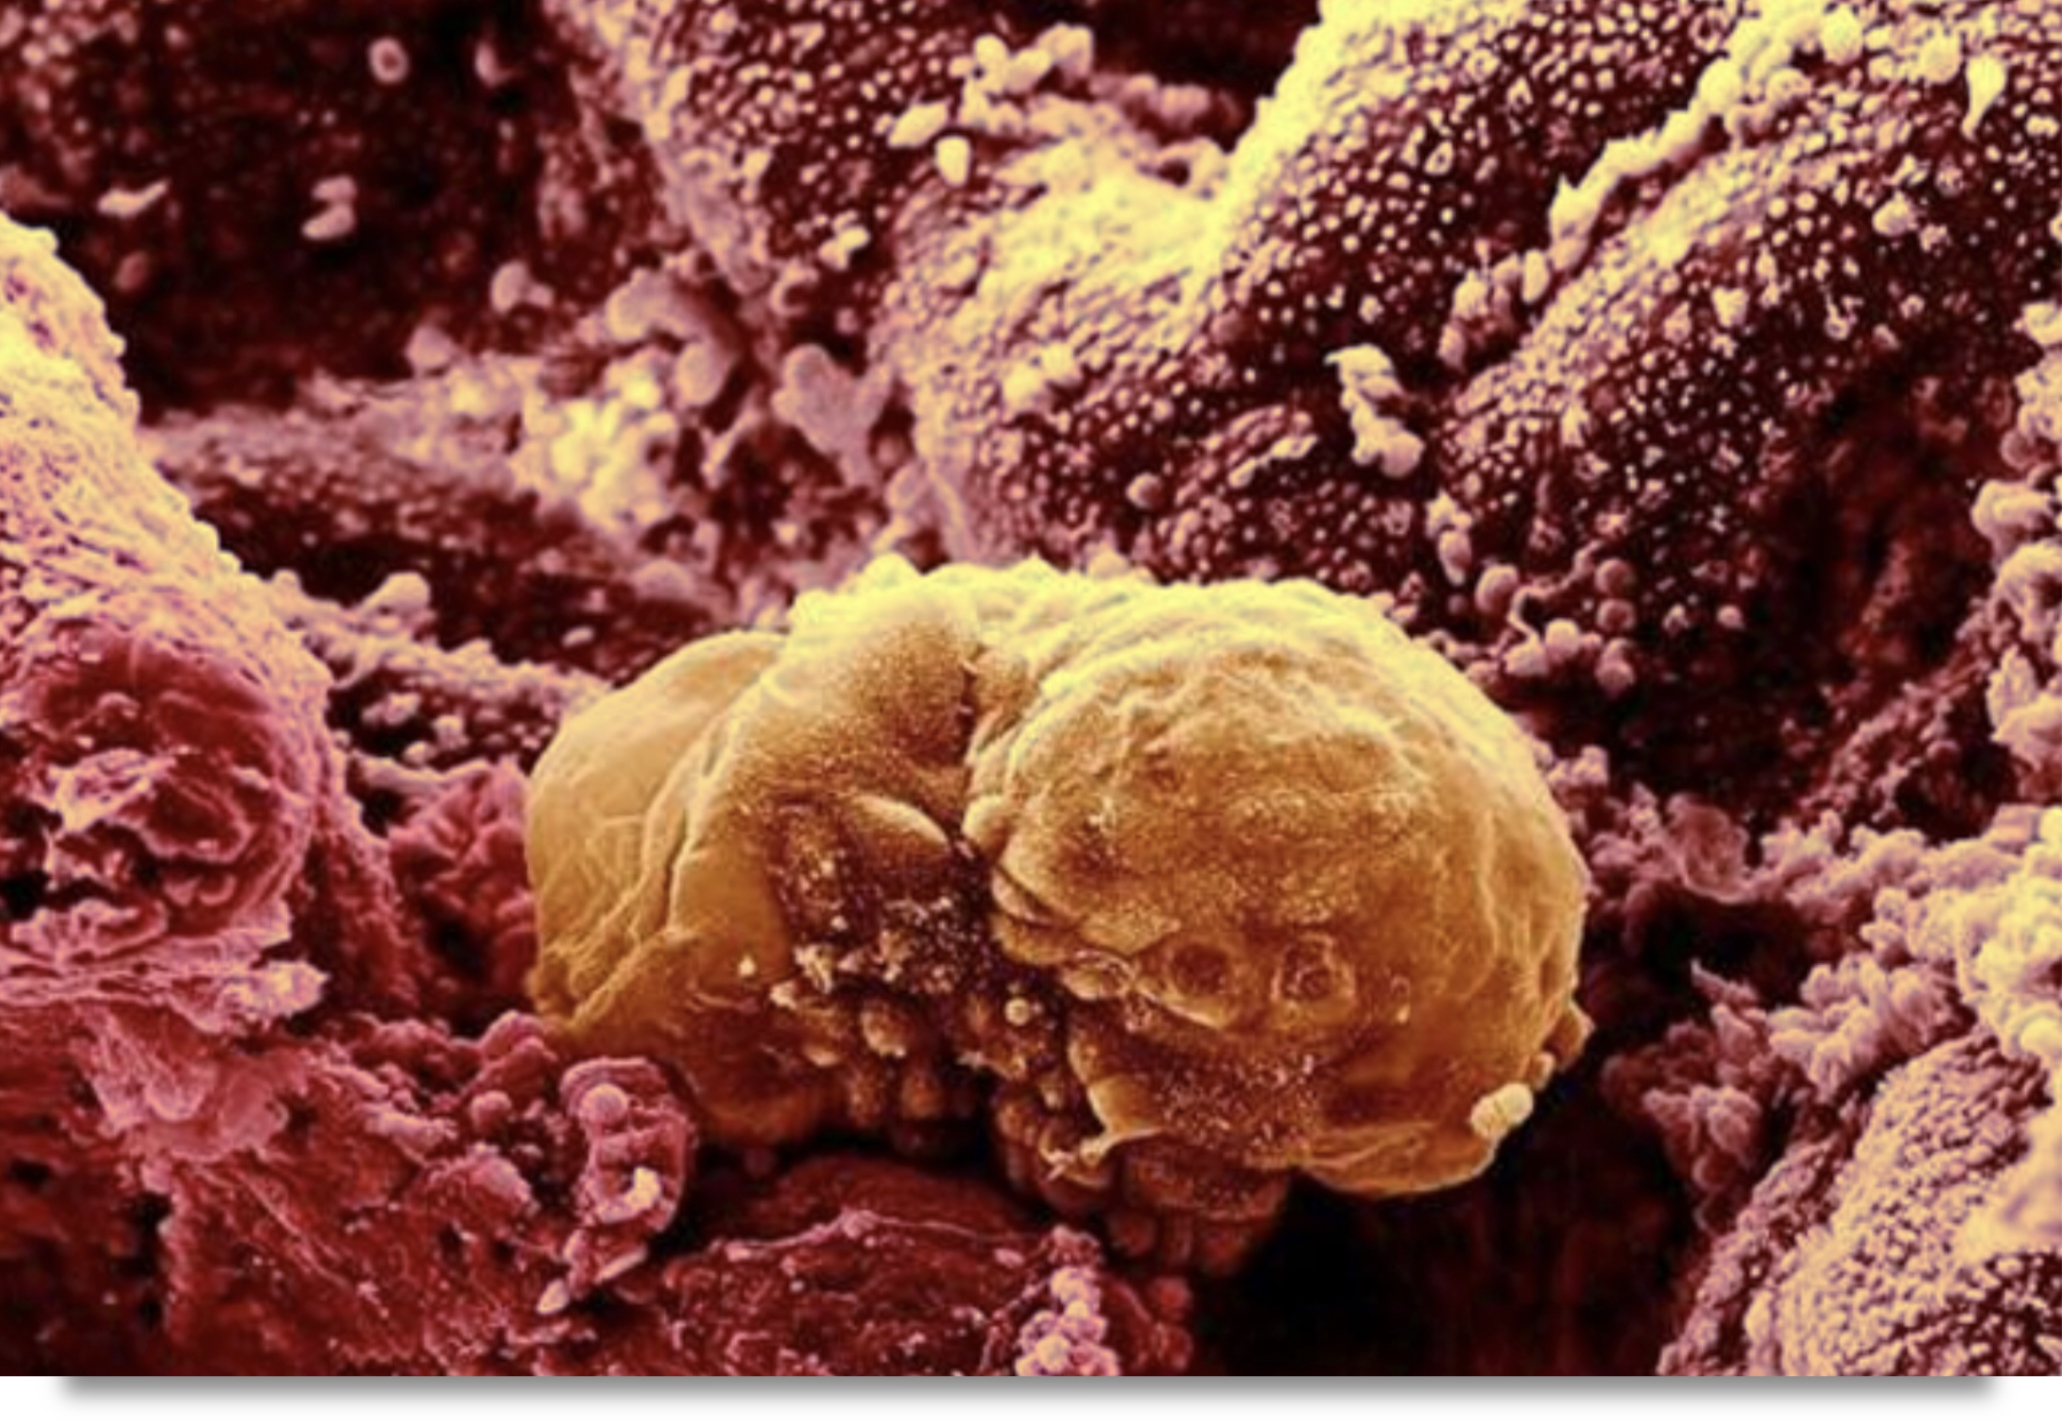

Tüp bebek neden tutmaz. Canım ben de menogon iğne ve klomen kullandım sadece 3 yumurtam oluşmuş çatlatma iğnesi verdi bugün olucam ertesi gün için aşılama dedi ama eşim aşılamayı istemiyor bizde kendimiz deniycez senin nasıl oldu bilgi verir misin. En az 3 tüp bebek tedavi girişiminde iyi kalitedeki embriyo transfer edilmesine karşın hamilelik oluşmaması ya da toplamda 10 ya da daha fazla embriyonun transferine rağmen hamilelik elde edilememesi tekrarlayan tüp bebek başarısızlığı diye adlandırılan bir durumdur. Mrb arkadaşlar menogon kullanan var mı ben ilk defa bu ay başladım daha 1 tane vuruldum bu iğneyle kaçıncı günde büyüdü yumurtalarınız ve bu yolla hamile kalanlar var mı forumlara baktım ama hep eski tarihli bende yeni bir konuda açmak istedim lütfen kullananlar bu forumda buluşalım.

Canımlar adetime az kaldı 3. İğne ile yapılan uyarıda daha fazla yumurta elde edildiğinden ve hapların rahim iç tabakası üzerine potansiyel olumsuz etkilerinden dolayı daha yüksek gebelik. Gonal f ve menogon kullanıp hamile kalanlar var mı. Kadından yumurta toplama ile elde edilen yumurta ve erkekten alınan spermin laboratuvar ortamında birleştirilmesi döllenmesi sonrası elde edilen embriyonun rahim içine nakledilmesidir.